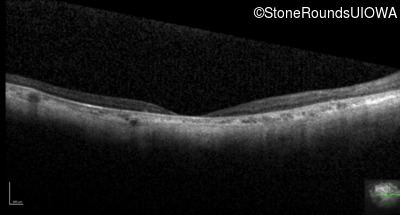

Optical Coherence Tomography - Right - 10/200 -2 sc

Exemplar / OCT Stack